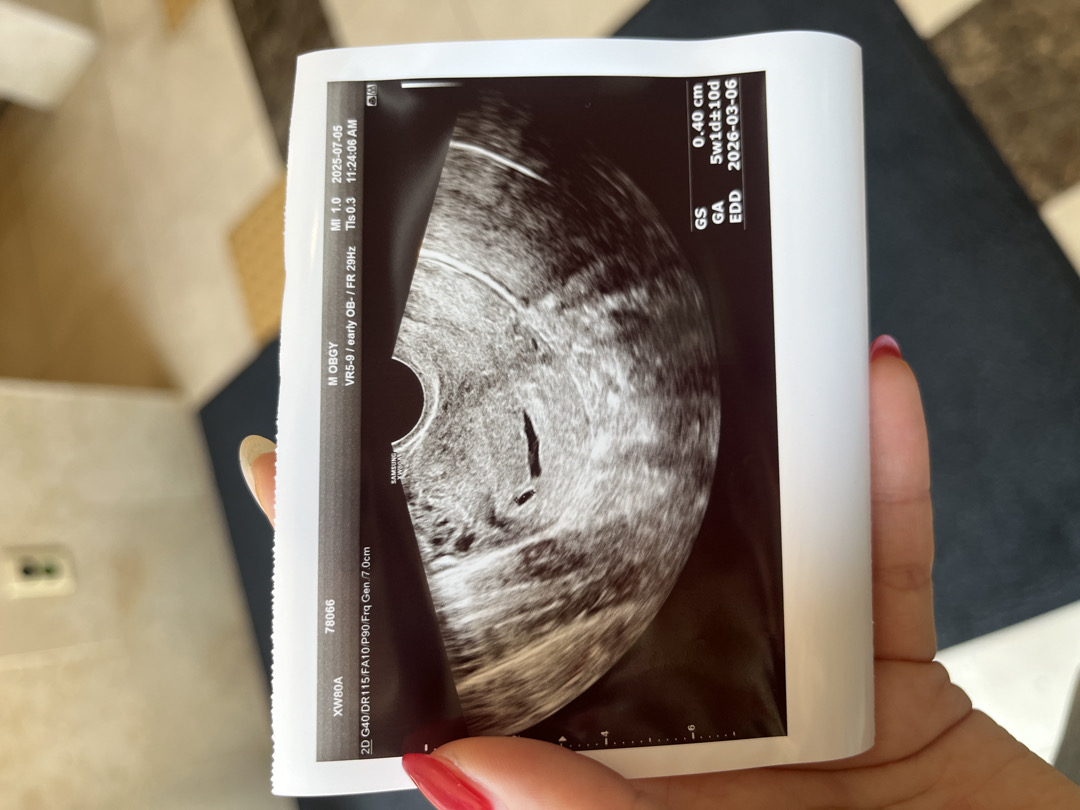

4주4일차 아기집 처음 봤어요!!

이제는 2주뒤에 오라고 하시는데 0.4cm면 괜찮은거겠죠?!

저도 4주4일차에 아기집 봤는데 0.34 하나 0.42 하나 였어요! 아기집 보기에는 이른주수라고 하긴하셨는데 그래서 조금 작은가봐요! ㅎㅎ 축하드려요!

맞아요 ㅠㅠ아직 너무 이르다고 하시더라구요!! 얼른 2주지나서 또 보고싶어요 🥹 축하드려요 ㅎㅎ